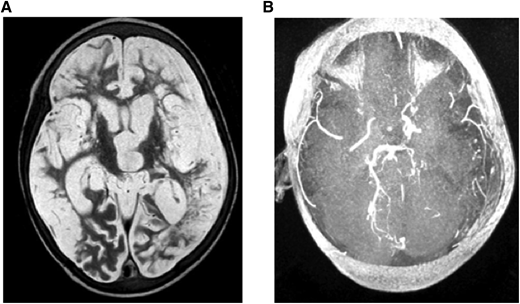

(A) MRI: T2W (axial) and (B) MRA. Brain images from a 7-year-old quadriplegic boy showing (A) global cerebral infarction and (B) occlusion of both terminal internal carotid arteries and small left posterior cerebral artery but no moyamoya collaterals.

(A) MRI: T2W (axial) and (B) MRA. Brain images from a 7-year-old quadriplegic boy showing (A) global cerebral infarction and (B) occlusion of both terminal internal carotid arteries and small left posterior cerebral artery but no moyamoya collaterals.